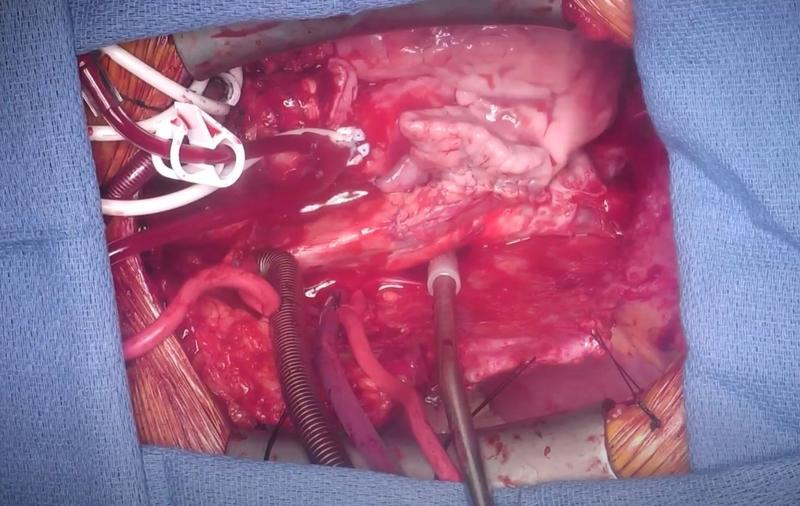

Chirurgii americani au transplantat cu succes o inimă dintr-un porc modificat genetic la un pacient, o premieră mondială, a anunțat luni Școala de Medicină a Universității din Maryland, scrie AFP. Operația a fost efectuată vineri, 7 ianuarie, și a arătat pentru prima dată că o inimă de animal poate continua să funcționeze în interiorul unui om fără respingere imediată, a precizat instituția, într-un comunicat.

David Bennett, 57 de ani, care a primit inima de porc, a fost declarat neeligibil pentru un transplant uman. Acum este monitorizat îndeaproape de medici, pentru a se asigura că noul organ funcționează corect. "Am avut de ales, să mor sau să fac acest transplant. Vreau să trăiesc. Știu că este destul de greșit, dar a fost ultima mea opțiune", a spus rezidentul din Maryland, cu o zi înainte de operație, potrivit Şcolii de Medicină. „Abia aștept să pot să mă dau jos din pat, odată ce voi fi bine”, a spus Bennett, care a petrecut ultimele luni țintuit la pat și conectat la un aparat care l-a ținut în viață. Autoritățile americane au dat undă verde operației în ajunul Anului Nou. „Aceasta este o descoperire chirurgicală majoră și una care ne aduce cu un pas mai aproape de o soluție la deficitul de organe”, a comentat Bartley Griffith, care a efectuat transplantul.

Porcul din care provine inima a fost modificat genetic pentru a nu mai produce un tip de zahăr care este prezent în mod normal în toate celulele de porc și care provoacă respingerea imediată a organului de către organismul uman.